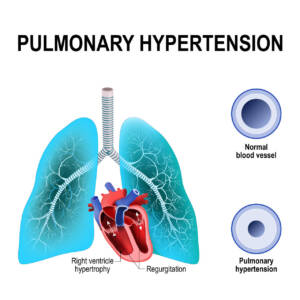

Nella Pneumologia: da utilizzare in caso di asma,

BPCO e ipertensione polmonare.

- della patologia da discrasia ventilatoria polmonare